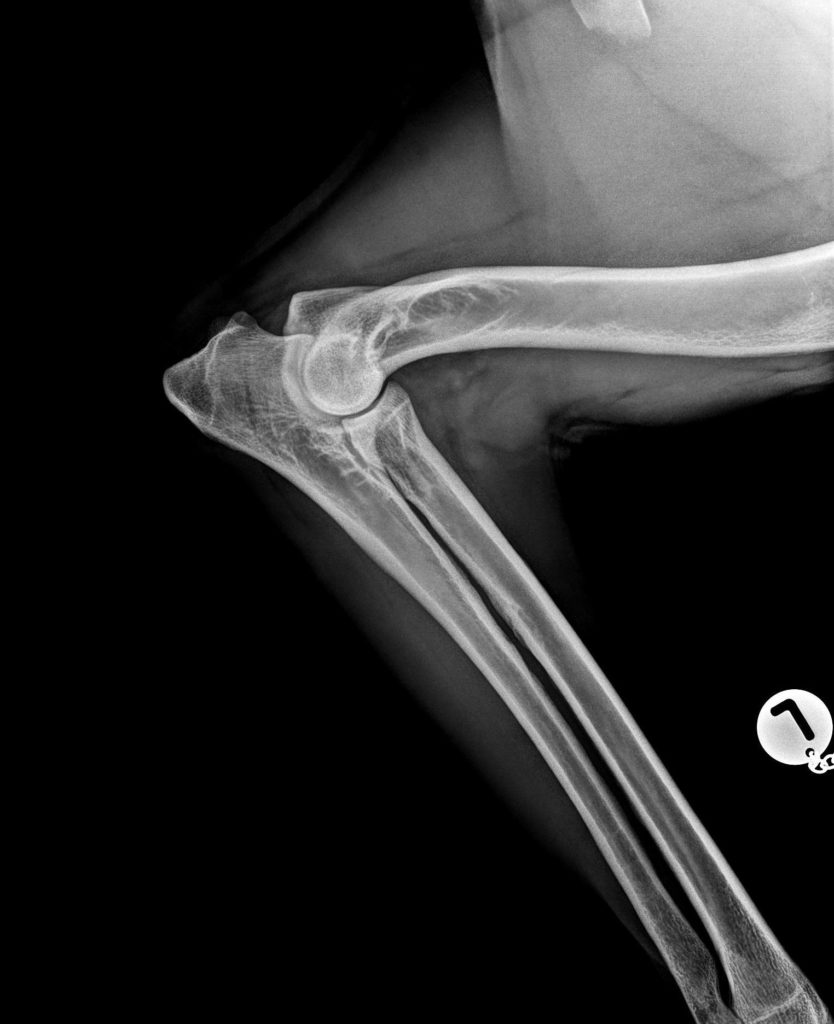

Richtlinien für die ED (Ellbogendysplasie) Röntgenaufnahmen

a. Mediolaterale Aufnahme (Abb. 1)

Ellbogen leicht gebeugt/ Öffnungswinkel zwischen 45° und 90°. Der Processus Anconaeus muss deutlich sichtbar und sein Verlauf nachvollziehbar sein. Um exzessive Pronation oder Supination des Unterarms zu vermeiden, empfiehlt sich das Beugen des Karpalgelenks und Lagerung parallel zu der Tischplatte.

BorakVet-Richtlinien ED Röntgenaufnahme

Abb. 1